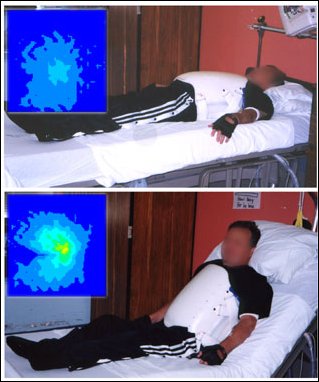

Pozycja podczas jakiej pacjent przebywa w łóżku może stanowić następny problem. U pacjenta na zdjęciu 8 podczas leżenia płasko w łóżku Mapa Ucisku jest zadawalająca. Kiedy oparcie zostaje podniesione, zwiększa się nacisk na kość ogonową. Nawet jeśli materac jest najlepszej jakości, to długie przebywanie w takiej pozycji może doprowadzić do powstania odleżyny, zatem należy ograniczyć spędzanie dłuższego czasu w takiej pozycji.

Zdjęcie 8: Mapa Ucisku podczas leżenia płasko na łóżku wygląda dobrze (zdjęcie górne), jednak podczas siedzenia na łóżku ucisk zwiększa się ewidentnie.